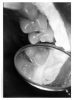

Figure 3 - Dentin Caries

Figure 3